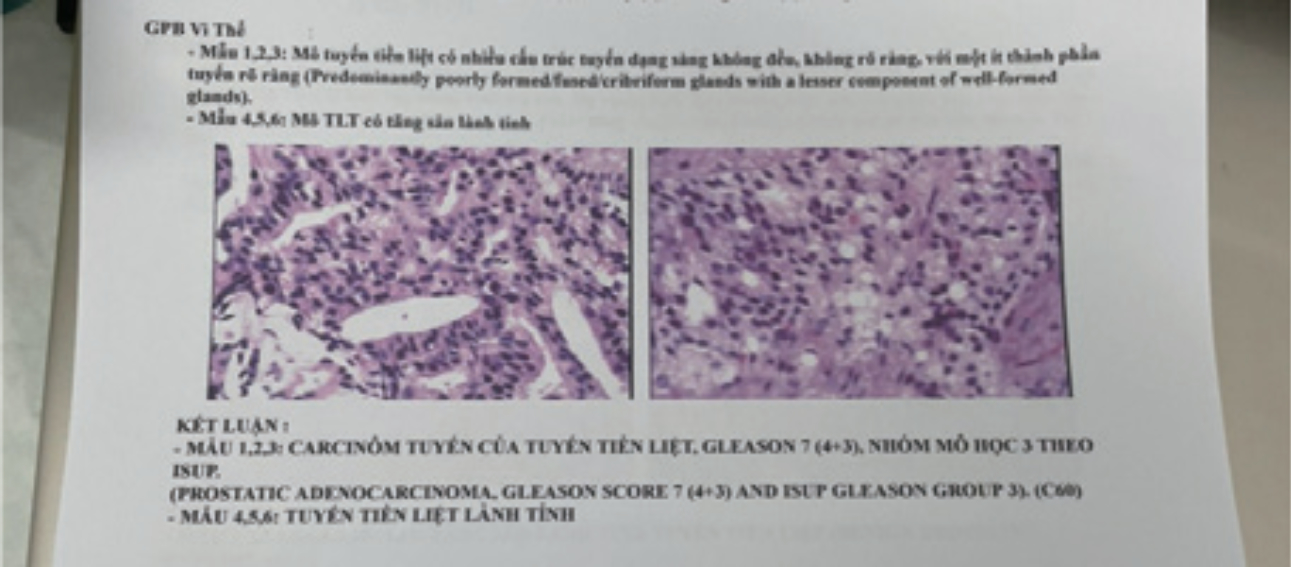

6 ?? ?? ??? ?????, 1~3? ??? ???? 4~6? ??? ???? ???????.

?

?? ?? ??

1,2,3: PROSTATIC ADENOCARCINOMA, Gleason score 7 (4+3), ISUP Gleason group 3 (C60): ??? ???? ??/??/???? ???? ????? ??? ???.

4,5,6: ?? ??? ??